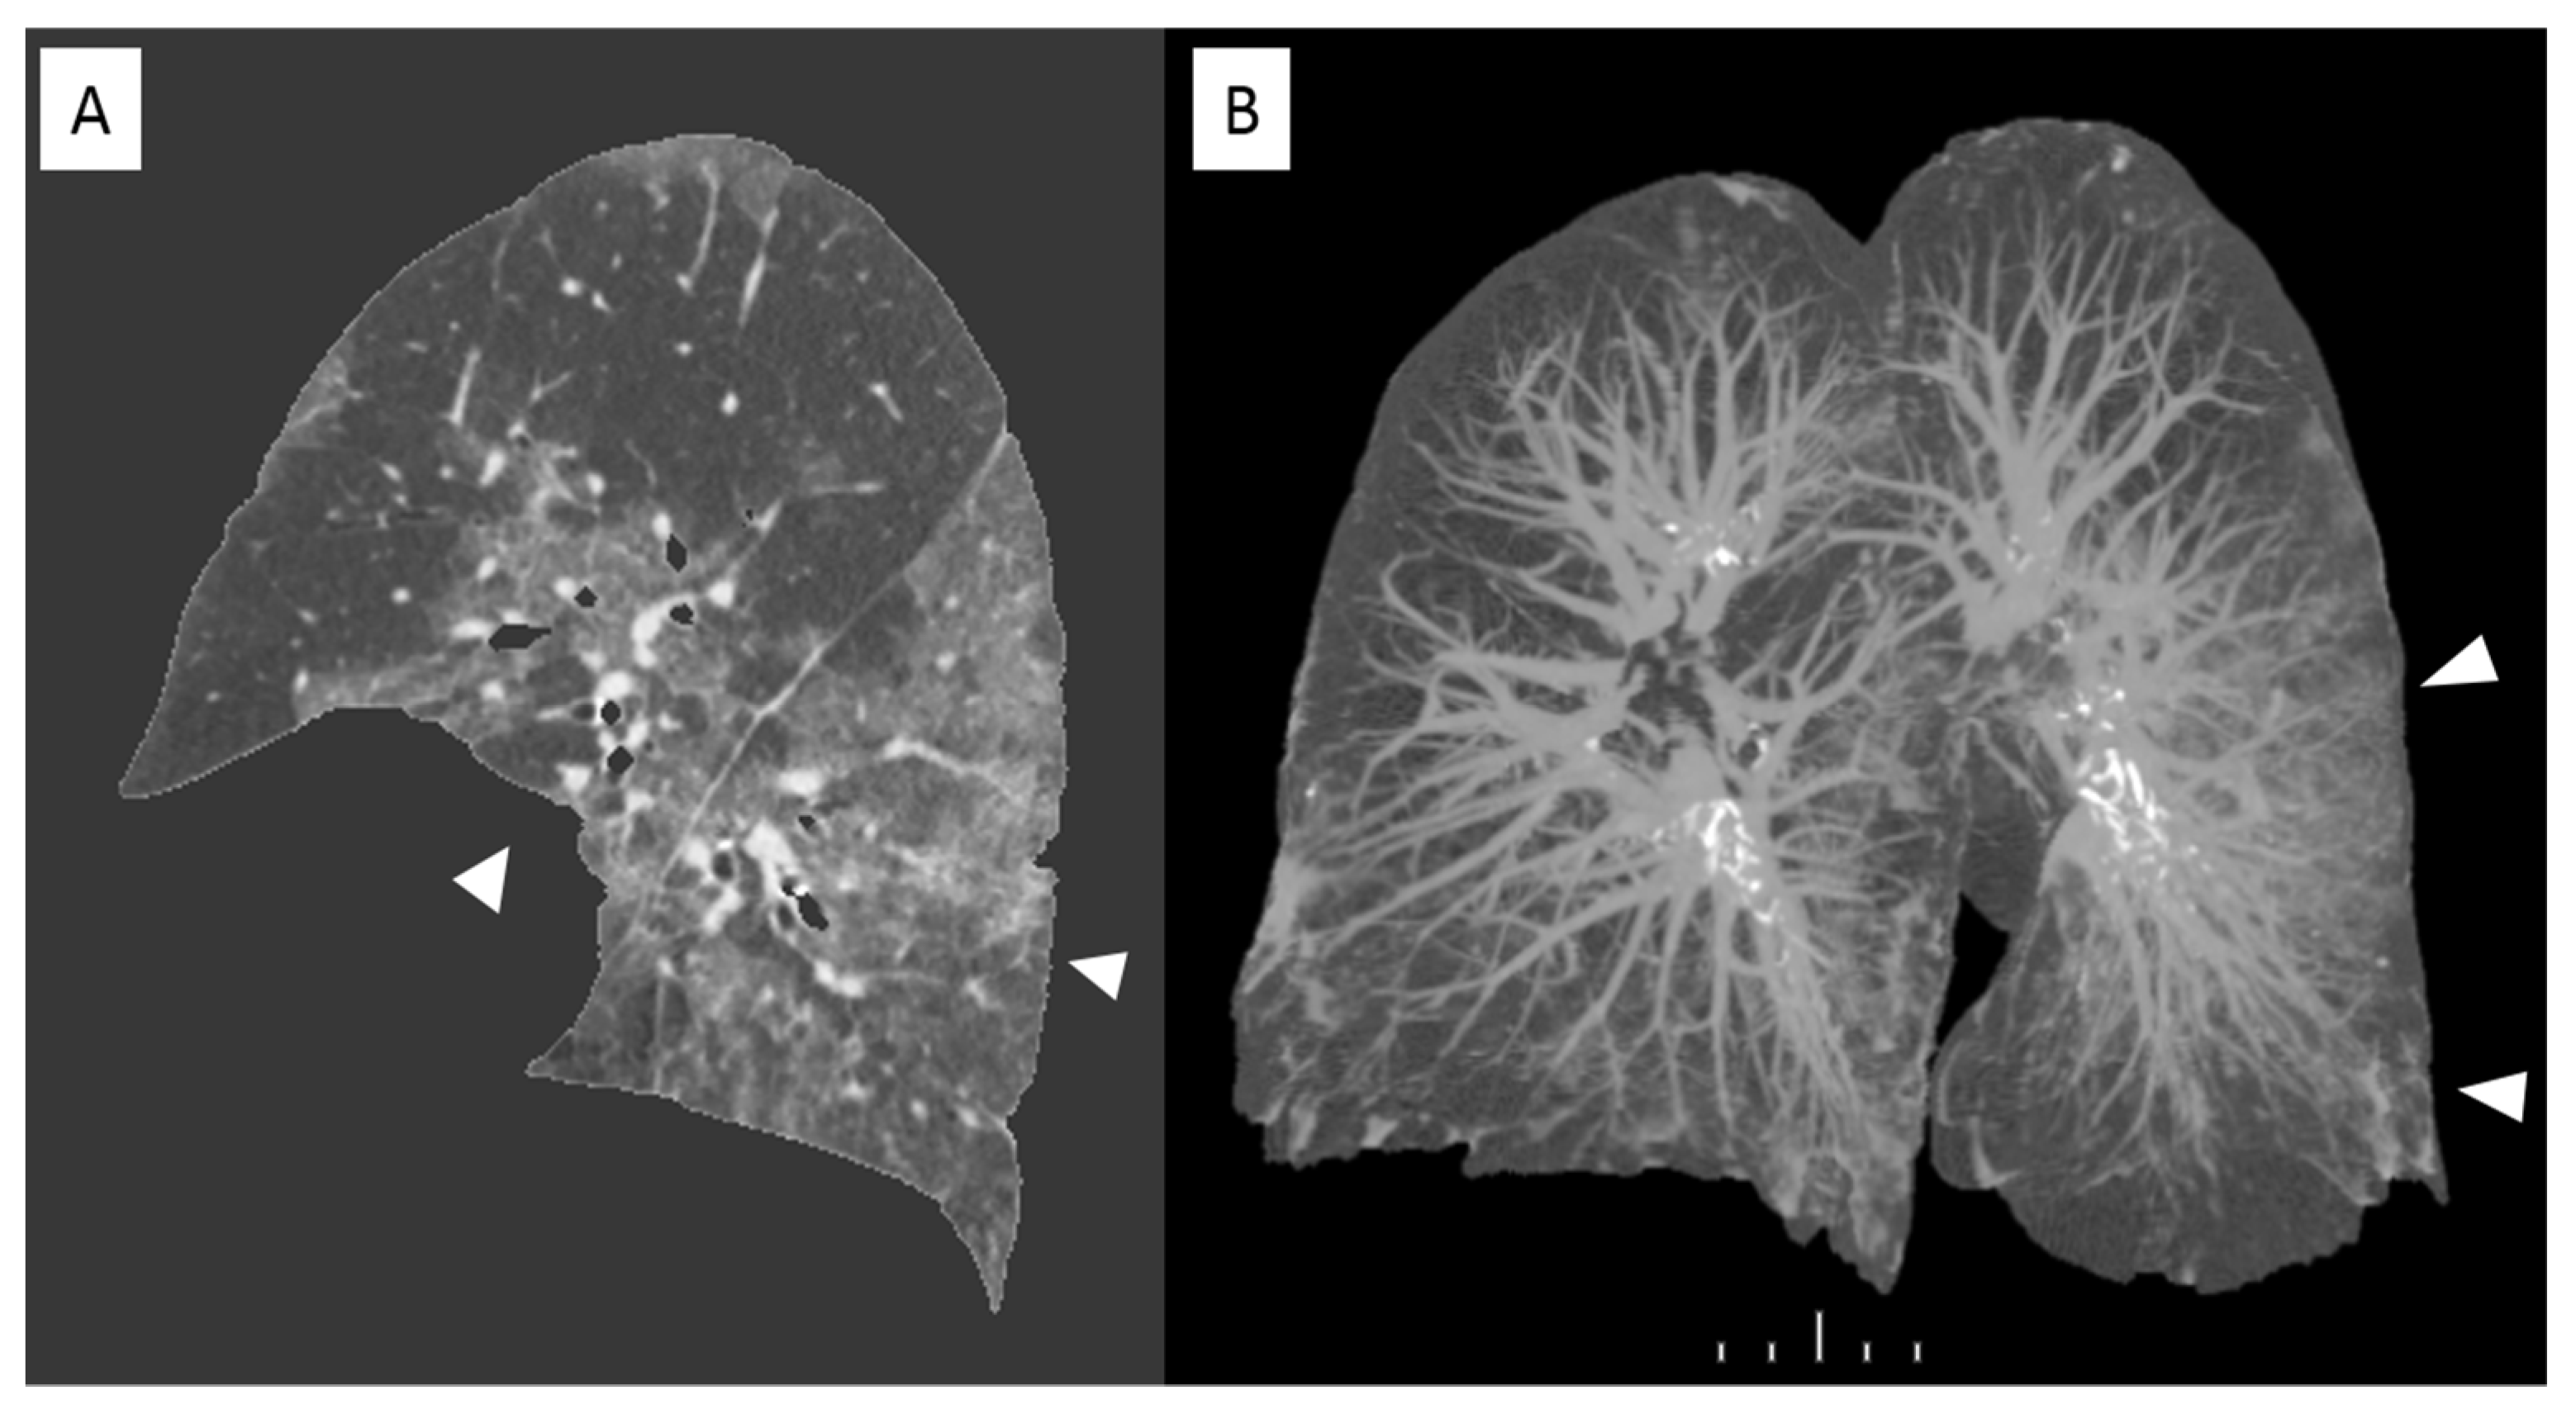

Recent studies have demonstrated that in case of viral pneumonia inter-observer reliability for CT scans can be reduced for determining the presence of intra-lobular reticulation, distribution of consolidation, and GGO [14]. And this can be observed in case of COVID-19 assessment because of features overlapping. In this scenario computer-aided lung volume quantification has been demonstrated as a feasible way to stratify COVID-19 cases according to extension and severity [15]. Figure 4 shows a volume rendering reconstruction of the lung volume.

Figure 4. Sagittal view of a non-enhanced CT with software segmentation (A) showing extended GGOs (arrowheads). On the right the volume rendering recon of the same CT (B) highlighting the pulmonary vessels and the infected parenchyma hyperdense (arrowheads). in comparison with adjacent normal aerated lung.